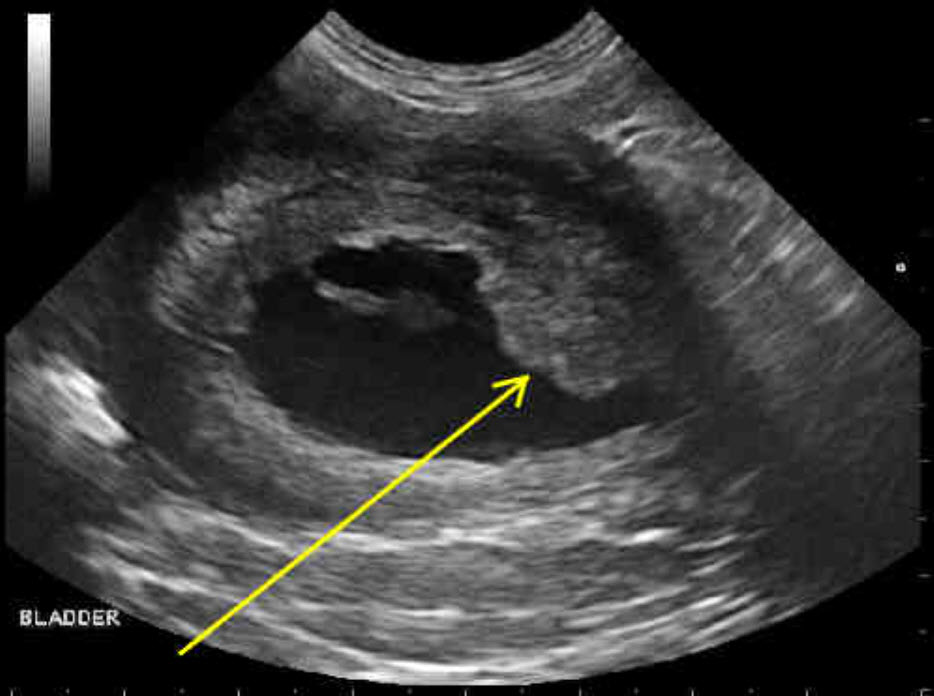

Canine transitional cell carcinoma of the urinary bladder a focus on Cat Bladder Ultrasound The urinary bladder is best visualized if it is full of urine; Ultrasound examination of the kidneys and perinephric space can provide important information on several conditions including chronic renal disease, hydronephrosis and perinephric pseudocyst formation. Therefore, do not let your cat urinate within three to six hours of the ultrasound procedure if possible. Ultrasound of the urinary bladder move. Cat Bladder Ultrasound.

From journals.sagepub.com